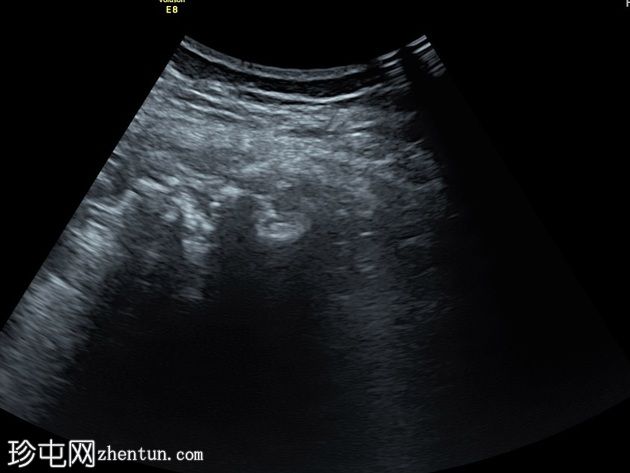

超声

纵切面

患者在局部麻醉下接受了超声引导下经左侧股骨受损皮质的活检。

病例讨论

本病例经组织病理学检查确诊为结核病。因此,最终诊断应包括左侧髋关节结核性关节炎,以及左侧股骨颈和股骨粗隆间结核性骨髓炎,并伴有大腿和臀肌内两个冷脓肿的形成。